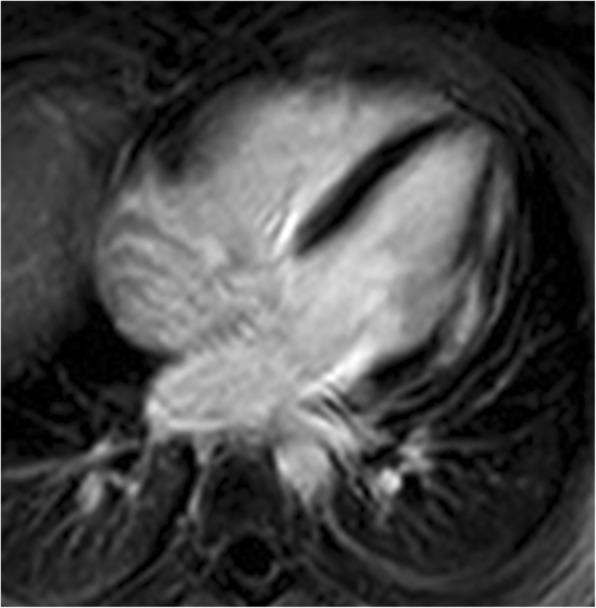

The progressive cardiomyopathy that develops in boys with Duchenne and Becker muscular dystrophy (DMD/BMD) is presumed to be a secondary consequence of the fibrosis within the myocardium. There are only limited data on using parametric imaging in these patients. The purpose of this study was to assess native T1 and extracellular volume (ECV) values in DMD patients.

The Czech population of males with DMD/BMD was screened. All eligible patients fulfilling the inclusion criteria were included. Forty nine males underwent cardiac magnetic resonance (MR) examination including T1 native and post-contrast mapping measurements. One DMD patient and all BMD patients were excluded from statistical analysis. Three groups were compared - Group D1 - DMD patients without late gadolinium enhancement (LGE) (n = 23), Group D2 - DMD patients with LGE (n = 20), and Group C - gender matched controls (n = 13).

RESULTS

Compared to controls, both DMD groups had prolonged T1 native relaxation time. These results are concordant in all 6 segments as well as in global values (1041 ± 31 ms and 1043 ± 37 ms vs. 983 ± 15 ms, both p < 0.05). Group D2 had significantly increased global ECV (0.28 ± 0.044 vs. 0.243 ± 0.013, p < 0.05) and segmental ECV in inferolateral and anterolateral segments in comparison with controls. The results were also significant after adjustment for subjects' age.

CONCLUSION

DMD males had increased native T1 relaxation time independent of the presence or absence of myocardial fibrosis. Cardiac MR may provide clinically useful information even without contrast media administration.